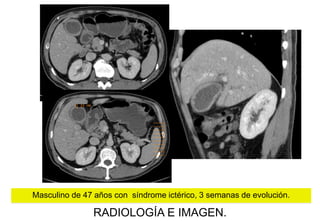

Masculino de 47 años con síndrome ictérico, 3 semanas de evolución.

Imagen coronal y axial TC , donde se observa aumento del tamaño de la

Imagen axial TC fase arterial,

aumento difuso del tamaño del

con reforzamiento homogéneo

leve-moderado (77.1 UH )

y dilatación del colédoco (1.7 cms).

Imagen axial TC , en fase venosa

donde persiste retardo en la

perfusión del páncreas

(79.5UH), SIN evidencia de

lesión focal en la

glándula pancreática

Fase tardía TC,

páncreas con 63.5UH.

Dilatación vías biliares

intrahepaticas

IMPRESIÓN TOMOGRÁFICA:

Acorde con la literatura, con la

aumentada de tamaño de

forma difusa, en forma de

¨salchicha¨, de predominio

hacia la cabeza, con

atenuación homogénea y

reforzamiento moderado son

hallazgos de:

PANCREATITIS

AUTOINMUNE

Masculino de 64 años de edad con SxDAA CSD y sindrome icterico